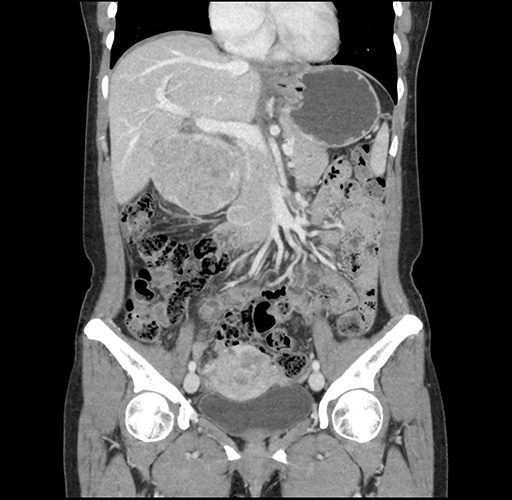

Imaging Analysis

Look through the patient's CT scan to identify any areas of concern for the necessary procedure.

Based on your CT findings, which issue(s) would give reason for "planned slowing down moment(s)" in this case?

Considering a standard left lateral sectionectomy procedure, what step(s) of the operation would you do differently in this case ?